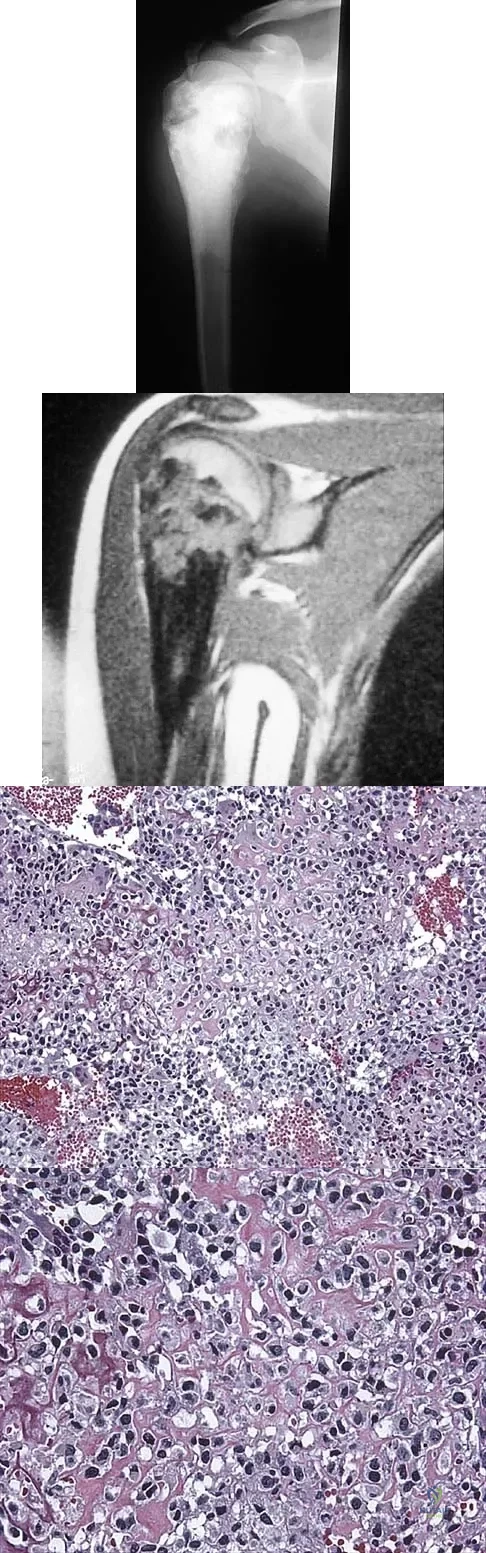

A 13-year-old girl has had a firm mass and pain in her right shoulder for the past several weeks. She denies any history of trauma. A radiograph and MRI scan are shown in Figures 31a and 31b. Biopsy specimens are shown in Figures 31c and 31d. What is the most likely diagnosis?

Explanation:

The patient has osteosarcoma. The radiograph suggests an aggressive primary tumor of bone, and the histology shows malignant cells surrounded by osteoid, classic for osteosarcoma. Ewing's sarcoma histologically consists of small round blue cells. Osteochondroma and periosteal chondroma occur in the shoulder but have a different histologic pattern and a less aggressive radiographic appearance. Chondrosarcomas rarely occur in children. Simon MA, Springfield DS, et al: Osteogenic Sarcoma: Surgery for Bone and Soft Tissue Tumors. Philadelphia, PA, Lippincott Raven, 1998, p 266.